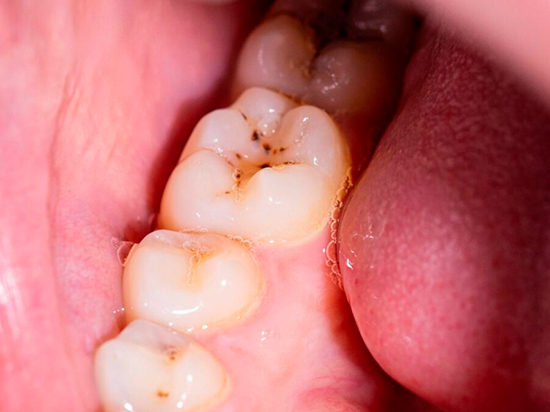

Las caries son una de las enfermedades bucales más comunes y pueden afectar a personas de todas las edades. Se producen por la acción de bacterias que, al metabolizar los azúcares de los alimentos, generan ácidos que desmineralizan el esmalte dental.

Primero definiremos que son las caries y que las crea, le llamamos carie a la afectación de nuestros dientes debido a las bacterias que se crean debido al consumo de bebidas azucaradas, postres o caramelos...